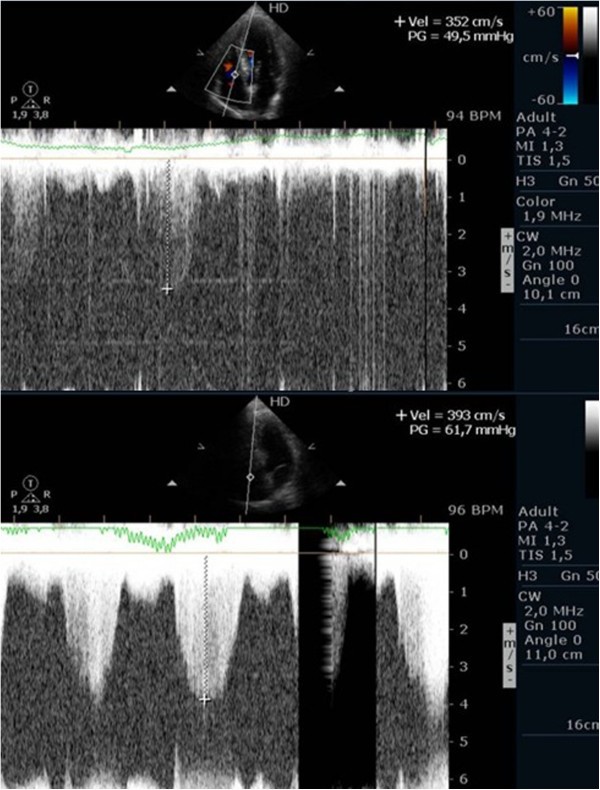

Evaluating pulmonary artery systolic pressure at rest using echocardiography is common practice and of considerable clinical importance [28]. A diagnosis of pulmonary arterial hypertension was based on a mean pulmonary artery pressure of >25 mmHg at rest or >30 mmHg during exercise [29]. Although routine assessment is generally carried out only at rest, the clinical importance of determining pulmonary artery systolic pressure during exercise has been demonstrated in various clinical conditions, particularly in mitral stenosis [30–33], mitral regurgitation [34] and rheumatologic disease [35]. Our group has published a study with patients having mitral stenosis. We assessed the right ventricle-right atrium (RV-RA) gradient using continuous wave Doppler in four stages: 1) left lateral decubitus before exercise testing; 2) in standing position; 3) at peak workload before termination of the test; 4) in the first 60 seconds of the recovery period in left lateral decubitus (Figure 3). The mean gradient between the left atrium and left ventricle was also determined at the different stages of the test in patients with mitral stenosis (Figure 4) (Additional file 4). We compared the variation of the gradient values between right ventricle and right atrium obtained at peak workload with those obtained only in the immediate recovery period. In this group of 56 patients with mitral stenosis, the decision to treat based on pulmonary artery systolic pressure of >60 mmHg determined by peak work load gradients between right ventricle and right atrium [30, 36] resulted in a positive net reclassification of 10 patients (18% of those with this pathology). These patients would have continued with medical therapy if the decision had been based on the values obtained during the recovery period, although peak overload RV-RA gradient measurement led to valvuloplasty or valve replacement referral. The results obtained for left atrium/left ventricle gradient influenced clinical decisions in three patients only, in whom no RV-RA gradient was detected at peak workload.

Left ventricular outflow tract obstruction is the major cause of symptoms in hypertrophic cardiomyopathy (HCM) and it has been associated to worse prognosis [67]. It is present in one-third of the patients at rest while the remaining two-thirds can be provoked [68, 69], nevertheless the best stress protocol is still yet to be defined. In our center, exercise echocardiography with image acquisition during treadmill exercise (considered to reflect exercise during daily activities) is commonly used in the evaluation of patients with HCM, enabling assessment of outflow gradient during physiologic exercise [7]. In these patients LVOT gradients increased in from supine to orthostatic position, and continued to augment at peak exercise, however after exercise the gradient decreased rapidly when measured in left lateral decubitus; the assessment of intra-ventricular gradient in recovery period in supine position probably does not reflect changes occurring immediately after effort [70] or the pathophysiology of this condition [68, 69, 71]. In a case report we stated that in one patient with HCM, the intra-ventricular gradient continued to increase if we maintained the patient in orthostatic position after exercise (Figure 11) (Additional files 10 and 11). Taking this into account, we performed a pilot study in 17 patients with HCM (11 with gradient above 30 mmHg under resting conditions) to determine the impact of orthostatism in the development of IVG in HCM [59]. Three patients without resting obstruction developed a significant intra-ventricular gradient during exercise; one patient only developed such a gradient in the recovery period in orthostatic position (Figure 12); two patients had neither resting nor exercise-induced obstruction. All patients with obstructive HCM increased IVG in orthostatic recovery. These results are different from those observed in our initial study [68] and from other studies in which the patients assume the supine position immediately after exercise [9, 72–76]. We have most recently expanded this observation to a cohort of 51 non-obstructive HCM patients, where similar results were obtained. The importance of orthostatic position in this particular group of patients as an additional and new stressor has also been underlined by other investigators [77–83]. All that considered this method may enhance the ability to evaluate patients with HCM and understand the mechanisms of symptoms. Laying the patients in supine position after any type of exercise may be meaningless from the clinical point of view, because this does not happen in real life. Future guidelines should clearly recommend a single methodology to be employed.